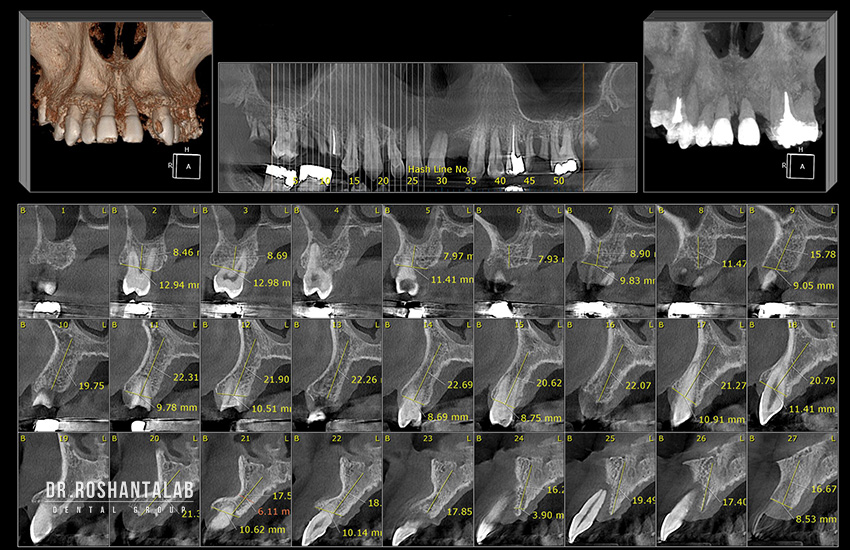

زمان مورد نیاز: 1 تا 2 روز همه چیز از یک معاینه دقیق شروع میشود. در این جلسه، متخصص ایمپلنت دکتر حسن روشن طلب وضعیت سلامت دهان، لثهها و دندانهای مجاور را بررسی میکند. مهمترین بخش این مرحله، انجام اسکن سه بعدی (CBCT) است. برخلاف عکسهای رادیوگرافی معمولی (OPG) که دو بعدی هستند، اسکن CBCT حجم دقیق استخوان، ضخامت آن، محل عبور اعصاب فک پایین و موقعیت سینوسها را به صورت میلیمتری نشان میدهد. دندانپزشک با نرمافزارهای شبیهسازی دیجیتال، محل دقیق کاشت را تعیین کرده و طرح درمان نهایی را به شما ارائه میدهد.

۴. از کجا بفهمم استخوان فک من برای ایمپلنت کافی است؟ تنها راه تشخیص قطعی، انجام اسکن سه بعدی (CBCT) است. در عکسهای رادیوگرافی معمولی سطح و عرض استخوان مشخص نیست. دندانپزشک با بررسی این اسکن کامپیوتری، ضخامت و تراکم استخوان را آنالیز میکند.